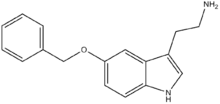

| 5-BT | artificial | 5-OCH2C6H5 | H | H | 5-Benzyloxytryptamine | 20776-45-8 |